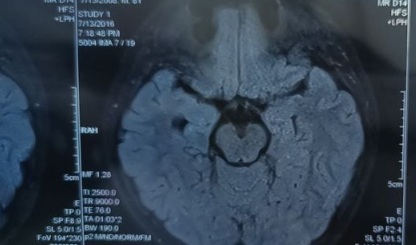

患者吳某,男,13歲。6年前無明顯誘因出現(xiàn)發(fā)作性雙眼凝視,意識不清,肢體抽搐,癥狀持續(xù)2--3分鐘后緩解,發(fā)作前有時會伴有頭痛、惡心、頭暈癥狀,數(shù)天發(fā)作一次,在多家醫(yī)院診斷為癲癇,右側(cè)海馬硬化,并先后給丙戊酸、奧卡西平、左乙拉西坦等藥物控制,但癥狀一直未完全控制,仍每月發(fā)作2--3次,后經(jīng)人介紹來我院就診,經(jīng)過我科診治以及多學(xué)科會診后建議考慮手術(shù)治療,家屬猶豫,給予調(diào)整藥物后發(fā)作次數(shù)減少,癥狀仍未完全控制,再次建議考慮手術(shù)治療。

該患者為典型的海馬硬化,顳葉癲癇,雖然歷經(jīng)坎坷,結(jié)果是好的。對于顳葉癲癇,特別是海馬硬化,一般是首選手術(shù)治療,有資料顯示80%顳葉癲癇患者手術(shù)效果好,80%顳葉癲癇患者藥物治療效果差,多數(shù)發(fā)展為難治性癲癇,僅有8%顳葉癲癇患者藥物治療有效,多數(shù)需終身用藥。所以對于顳葉癲癇患者,盡早行手術(shù)治療是首選。